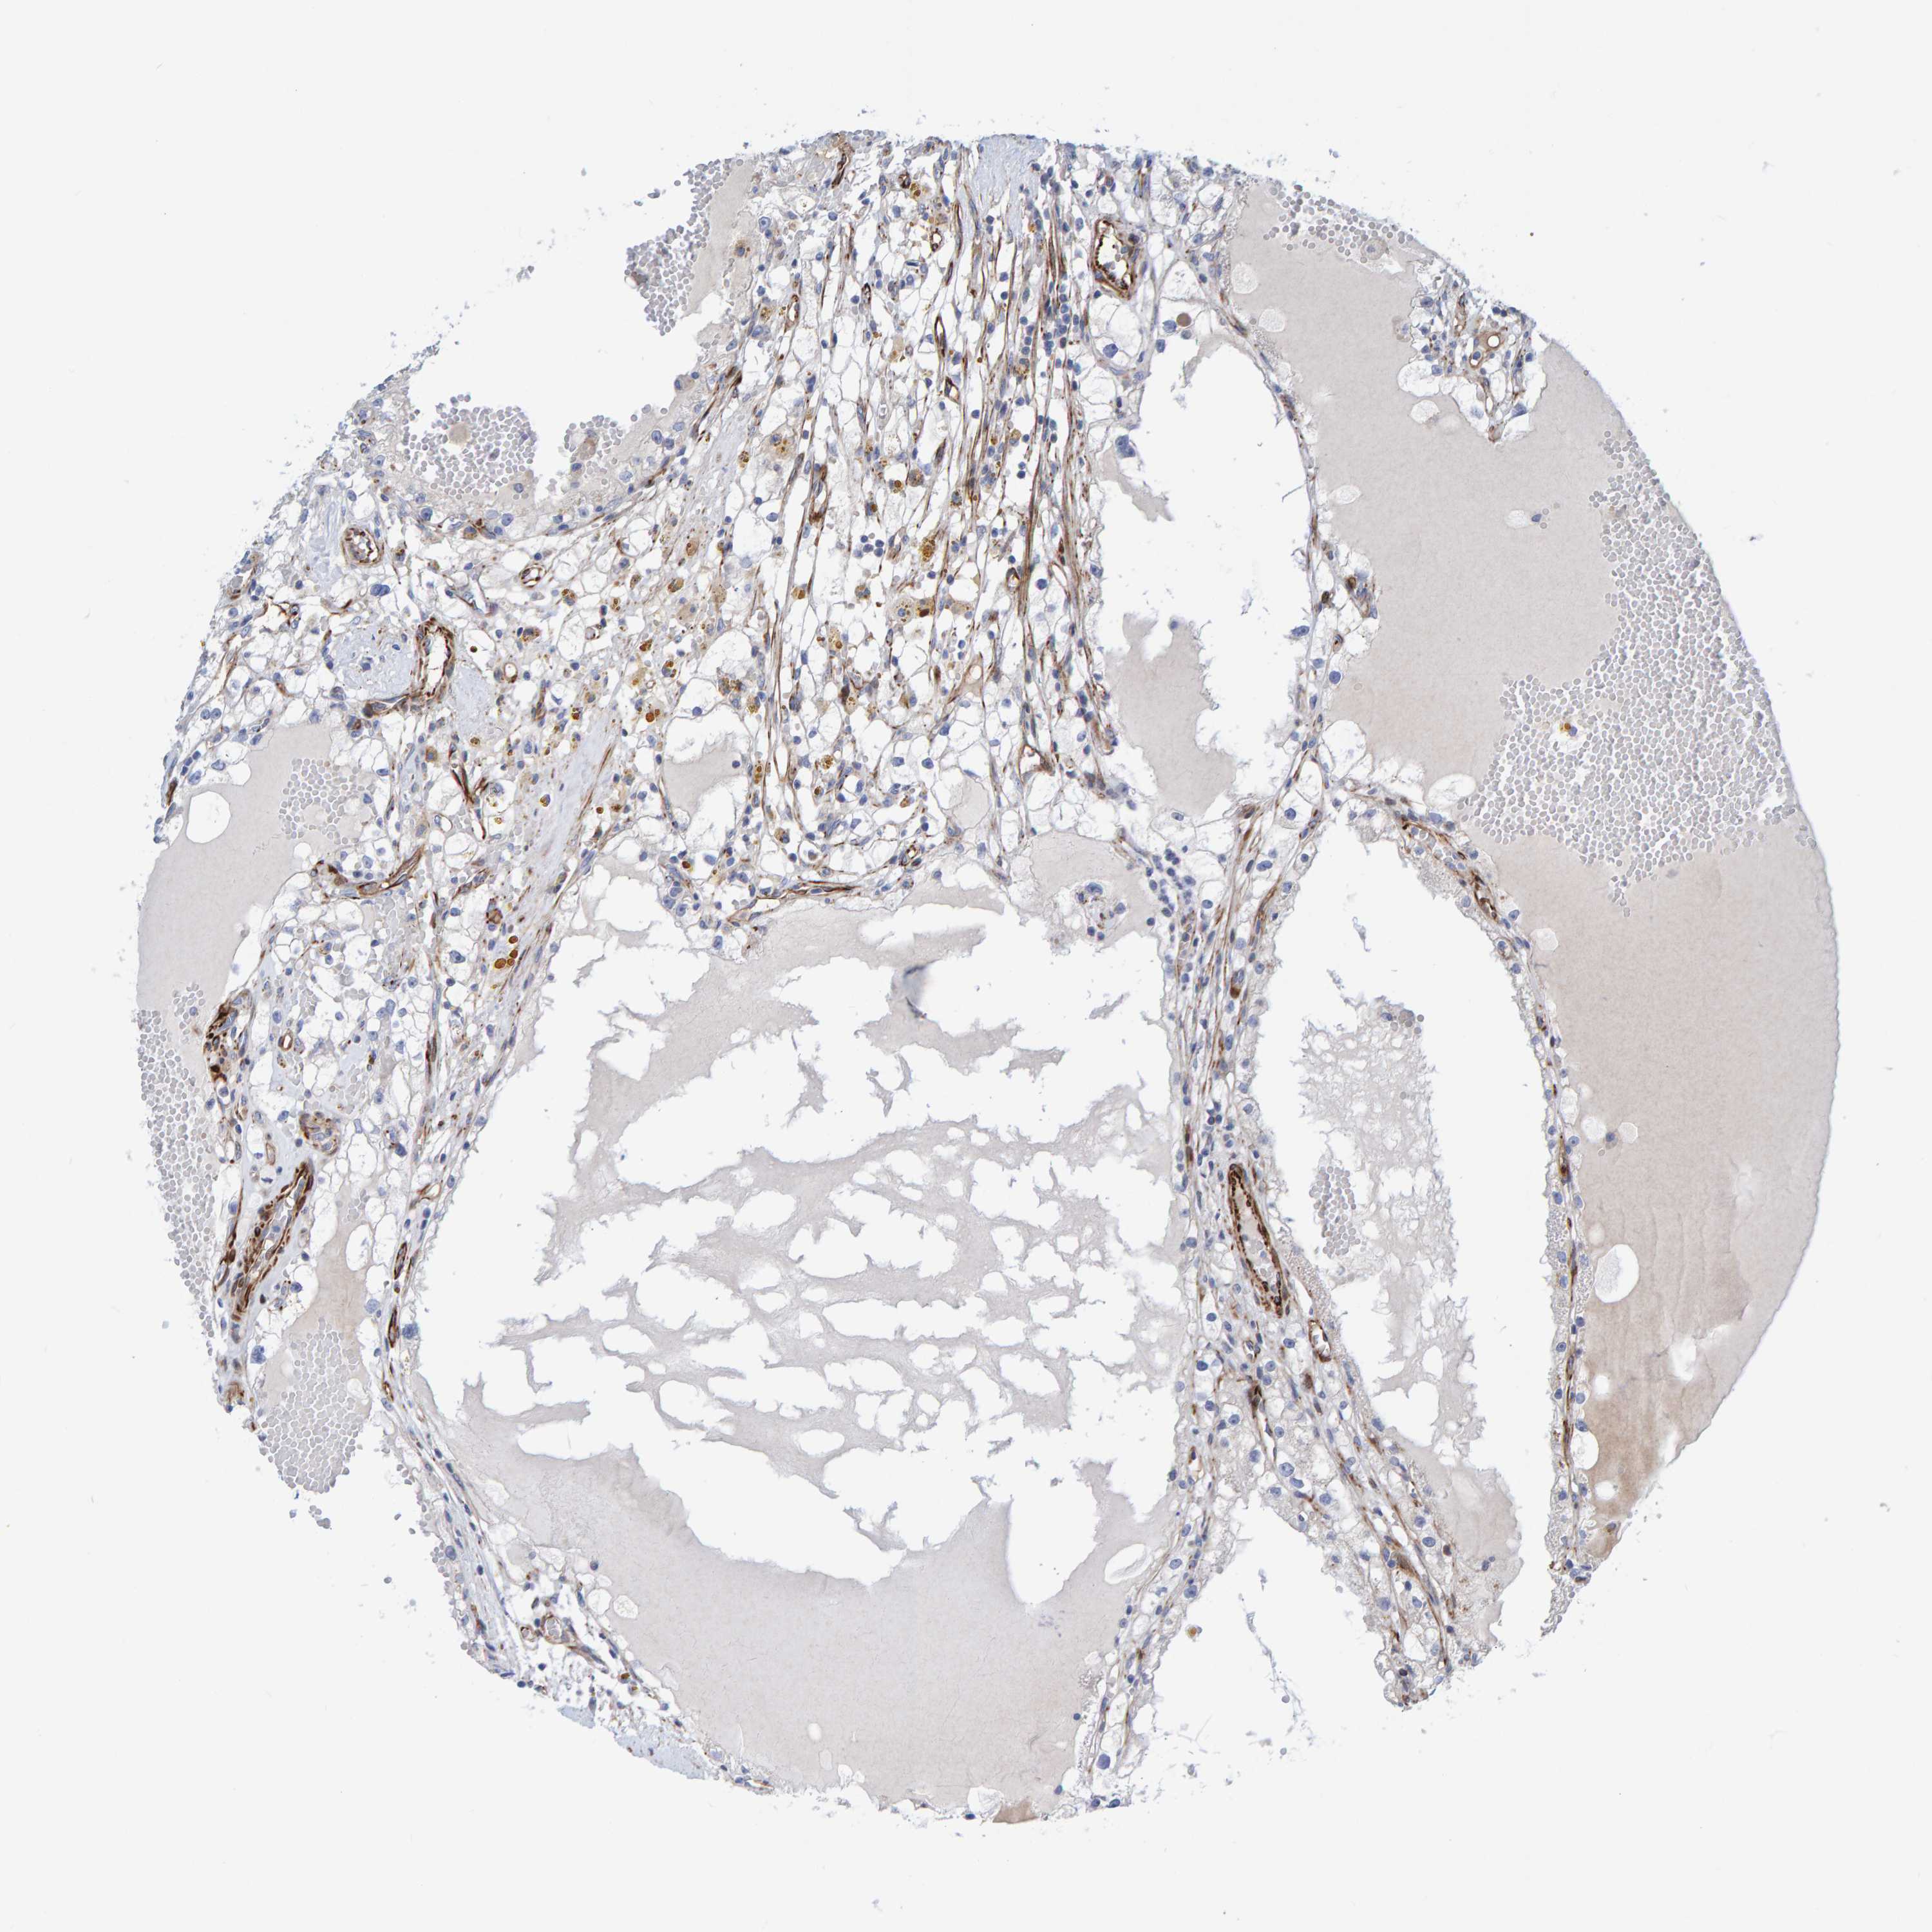

KIDNEY RENAL CLEAR CELL CARCINOMA (VALIDATION) - Interactive survival scatter ploti

The Survival Scatter plot shows the clinical status (i.e. dead or alive) for all individuals in the patient cohort, based on the same data that underlies the corresponding Kaplan-Meier plots. Patients that are alive at last time for follow-up are shown in blue and patients who have died during the study are shown in red.

The x-axis shows the expression levels (FPKM) of the investigated gene in the tumor tissue at the time of diagnosis. The y-axis shows the follow-up time after diagnosis (years). Both axes are complimented with kernel density curves demonstrating the data density over the axes. The top density plot shows the expression levels (FPKM) distribution among dead (red) and alive patients (blue). The right density plot shows the data density of the survived years of dead patients with high and low expression levels respectively, stratified using the cutoff indicated by the vertical dashed line through the Survival Scatter plot. This cutoff is automatically defined based on the FPKM cutoff that minimizes the p-score. The cutoff can be changed by dragging the vertical line or by entering a cutoff value in the square labeled "Current cut-off".

Under the Survival Scatter plot the p-score landscape (black curve; left axis) is shown together with dead median separation (red curve; right axis). Dead median separation is the difference in median mRNA expression between patients who have died with high and low expression, respectively. It is calculated as follows: median FPKM expression of dead patients with high expression - median FPKM expression of dead patients with low expression. This is intended to aid the user in visually exploring custom cutoffs and the associated p-scores and dead median separation.

Individual patient data is displayed and can be filtered by clicking on one or more of the category buttons on the top of the page. Categories describing expression level and patient information include: high, low, alive, dead, female, male and tumor stages. The scale of the x-axis can be toggled between linear and log-scale by clicking on the "x log" button. Mouse-over function shows TCGA ID, patient information and mRNA expression (FPKM) for each patient.

& Survival analysisi

Kaplan-Meier plots summarize results from analysis of correlation between mRNA expression level and patient survival. Patients were divided based on level of expression into one of the two groups "low" (under cut off) or "high" (over cut off). X-axis shows time for survival (years) and y-axis shows the probability of survival, where 1.0 corresponds to 100 percent.

POLG2 is not prognostic in Kidney Renal Clear Cell Carcinoma (validation)

Best expression cut offi

Based on the FPKM value of each gene, patients were classified into two groups and association between prognosis (survival) and gene expression (FPKM) was examined. The best expression cut-off refers the FPKM value that yields maximal difference with regard to survival between the two groups at the lowest log-rank P-value. Best expression cut-off was selected based on survival analysis .

When clicking on this number, the vertical dashed line indicating cut-off, the interactive survival plot, and the Kaplan-Meier curve will be adjusted to show results based on the best expression cut-off.

: 4.51

Median expressioni

Median expression refers to the median FPKM value calculated based on the gene expression (FPKM) data from all patients in this dataset. When clicking on this number, the vertical dashed line indicating cut-off, the interactive survival plot, and the Kaplan-Meier curve will be adjusted to show results based on the median expression.

: N/A

Median follow up timei

Median follow up time refers to the median time (years) after diagnosis with this type of cancer, based on clinical data from all patients in this dataset.

P scorei

Log-rank P value for Kaplan-Meier plot showing results from analysis of correlation between mRNA expression level and patient survival.

N/A

5-year survival highi

5-year survival for patients with higher expression than the expression cutoff.

For melanoma and glioma, 3-year survival is shown.

5-year survival lowi

5-year survival for patients with lower expression than the expression cutoff.

Average pTPM 6.1

Number of samples 100